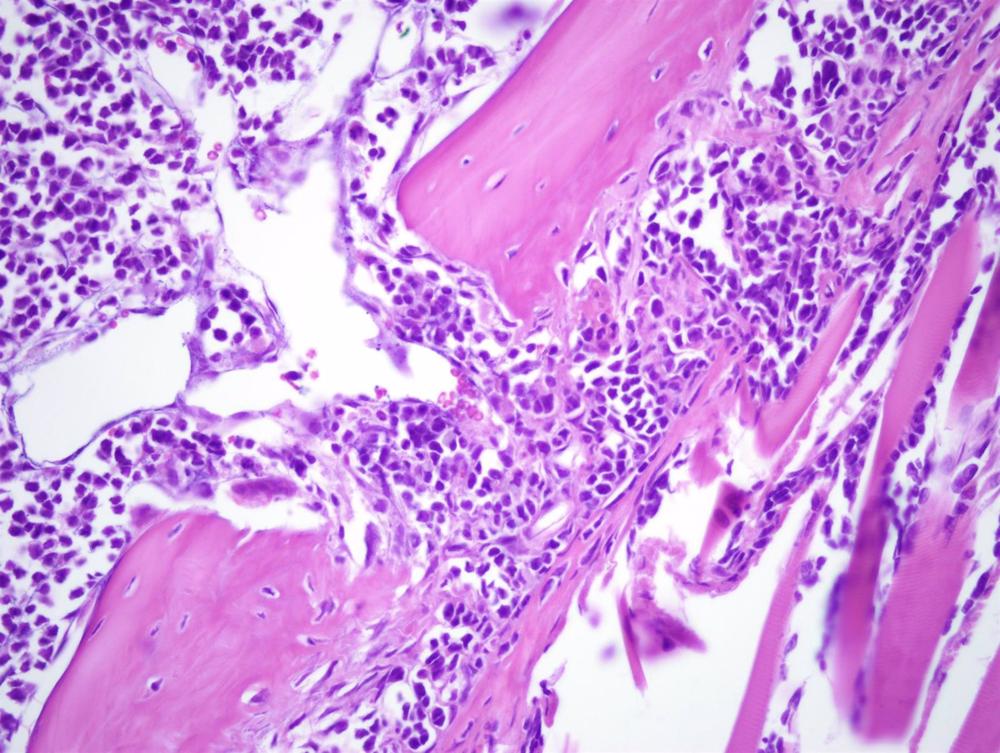

El mieloma múltiple es el tercer tumor hematológico en frecuencia, ya que representa el 1 por ciento de todas las neoplasias y el 10 por ciento de las neoplasias hematológicas. Se trata de un cáncer de las células plasmáticas, situadas en la médula ósea, cuyo rol es crucial en el sistema inmunitario.

En esta situación son necesarios nuevos tratamientos con mecanismos de acción distintos, como es la terapia con células CAR-T. Esta terapia consiste en la modificación genética en el laboratorio de los linfocitos T (una de las principales células del sistema inmune), de manera que se refuerce su capacidad de reconocer y destruir a las células tumorales.